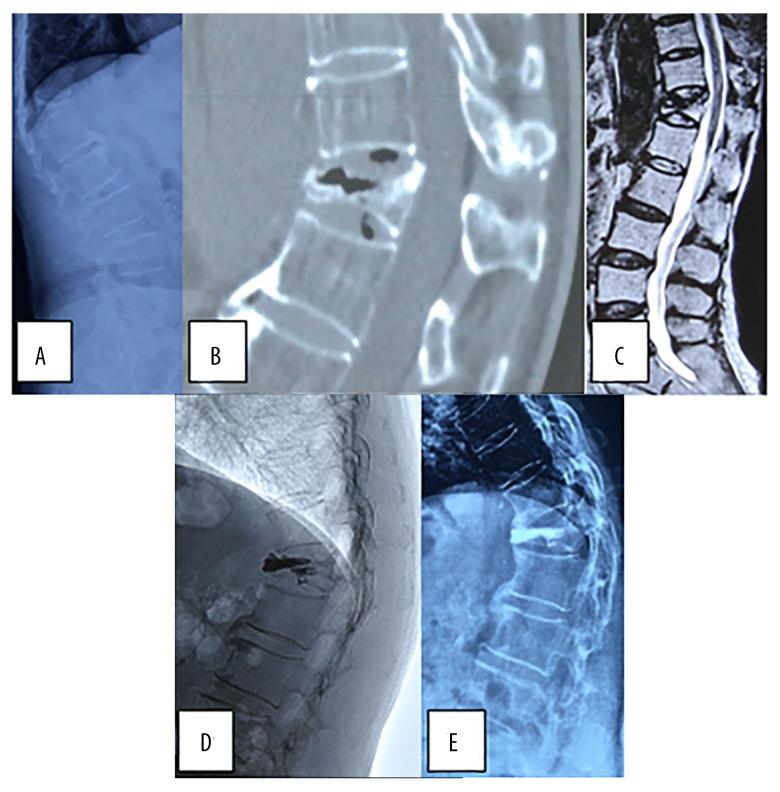

Comparison of Percutaneous Kyphoplasty and Bone Cement-Augmented Short-Segment Pedicle Screw Fixation for Management of Kümmell Disease.

BACKGROUND The purpose of this study was to compare the efficacy of percutaneous kyphoplasty (PKP) and bone cement-augmented short segmental fixation (BCA+SSF) for treating Kümmell disease. MATERIAL AND METHODS Between June 2013 and December 2015, 60 patients were treated with PKP or BCA+SSF. All patients were followed up for 12-36 months. We retrospectively reviewed outcomes, including Oswestry Disability Index (ODI), visual analogue scale (VAS), and kyphotic Cobb angle. RESULTS VAS, ODI, and Cobb angle, measured postoperatively and at the final follow-up, were lower than those measured preoperatively in both groups (P<0.05). VAS, ODI, and Cobb angle measured postoperatively demonstrated no significant differences when compared with those measured at the final follow-up in the PKP group (P>0.05). In the BCA+SSF group, VAS and ODI at the final follow-up were lower than those measured postoperatively (P<0.05), but no significant difference was found in the Cobb angle (P>0.05). The PKP group had better VAS and ODI than the BCA+SSF group, postoperatively (P<0.05). No significant difference was found in VAS and ODI at the final follow-up (P>0.05) or the Cobb angle measured postoperatively and at the final follow-up (P>0.05) between the 2 groups. Operative time, blood loss, and hospital stay in the PKP group were lower than those in the BCA+SSF group (P<0.05). No significant difference was found in complications (P>0.05). CONCLUSIONS PKP patients had better early clinical outcomes, shorter operation times and hospital admission times, and decreased blood loss, but had similar complications, radiographic results, and long-term clinical outcomes compared with BCA+SSF patients.